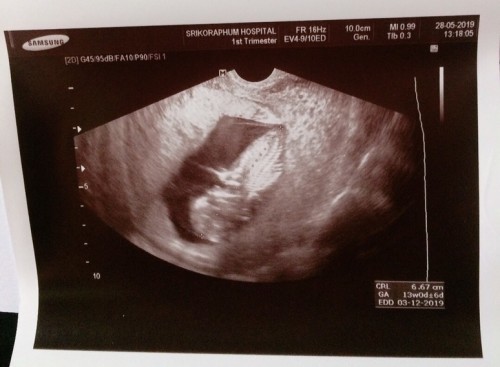

อัตราซาวค์เมื่อวันที่ 28 พ.ค เราสามารถนับย้อนหลังได้ไหมว่าวันที่ปฏิสนธิคือช่วงไหนค่ะ